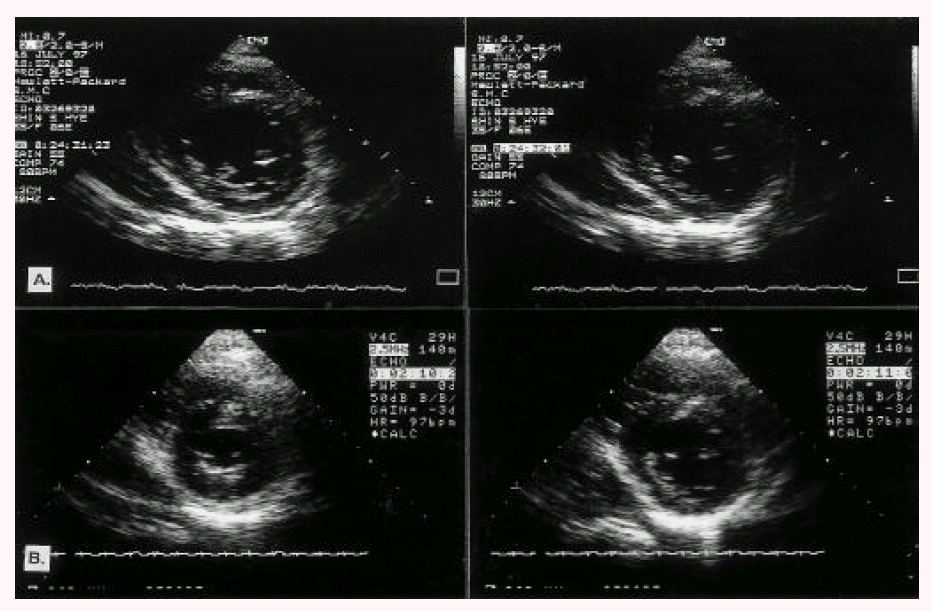

Fig. 2.

Transthoracic eohocardiographic findings (left panel: end-systole; right panel: end-diastole). A. Depressed left ventricular contraction and regional wall motion abnormalities. B. Increased left ventricular ejection fraction and recovered wall motion abnormalities after therapy.

Phenoxybenzamine was used to control the hypertension and metoprolol was added after the phenoxybenzamine use. Enalapril was prescribed to treat the myocardial damage. After medication, the patient’s blood pressure decreased to the normal range and her symptoms disappeared. Serial transthoracic echocardiography was performed on the second day after the medical management. It revealed a dramatic increase in the left ventricular ejection fraction (to 49%) and complete resolution of the regional wall motion abnormalities (Fig. 2). In the early treatment period, the patient complained of postural dizziness and there was evidence of postural hypotension. The dosage of phenoxybenzamine was reduced in order to prevent the development of such symptoms. A right adrenalectomy was performed after 20 days of medical management. The mass was 5×5 cm in size and there was no evidence of malignancy. After the surgery, the patient’s blood pressure was well controlled by metoprolol and enalapril without phenoxybenzamine. In the 24-hour urine collection after the right adrenalectomy, the total metanephrine level decreased to 0.5 mg/day and the VMA level was 4.5 mg/day. The baby was healthy without neonatal growth retardation, and the patient discharged without complication.

For the diagnosis of cardiomyopathy, serial electrocardiographs and cardiac enzyme follow-up are essential. As in our case, if the cardiomyopathy is properly managed, serial echocardiography could show progressively increased left ventricular ejection fraction and improved regional wall motion abnormalities3).